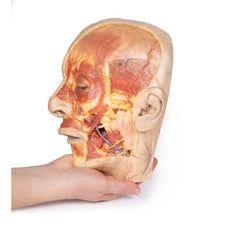

3D Printed Brain Hemisection

This 3D model is a midsagittal hemisection through a whole brain, preserving the right side anatomy and deep brain

structures and spaces visible in the midline. In lateral view, the right cerebral and cerebellar hemispheres are

covered in the arachnoid mater. In the midline view, the brain regions from the cerebrum to the medulla oblongata

are preserved. Centrally, the third ventricle is opened, with an intact septum pellucidum superiorly positioned and

obscuring the lateral ventricles within the cerebral hemisphere. On the inferior margin of the third ventricle both

the right mamillary body and right optic tract can be observed, whereas posteriorly the cerebral aqueduct can be

observed extending across the midbrain between the tectum and tegmentum towards the fourth ventricle (between the

cerebellum and pons). The cerebellum is separated from the occipital lobe by a preserved portion of the tentorium

cerebelli, and in cross-section the cerebellar cortex helps form the prominent arbor vitae.

A series of arterial

branches have been false coloured to contrast their course across the preserved brain structures. In the midsagittal

view the anterior cerebral artery courses from around the corpus callosum to supply the cingulate gyrus and other

midline cortical regions. The base of the middle cerebral artery can be seen passing deep between the temporal and

frontal lobes, with the posterior communicating artery connecting it to a small remnant of the posterior cerebral

artery. Adjacent to the posterior cerebral is the superior cerebellar artery, extending laterally to pass between

the temporal lobe and the cerebellum before passing deep into the transverse fissure.